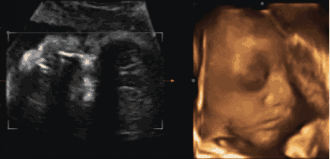

妈妈,这个月对你我来说都十分重要,现在你可以借助听诊器听到我强有力的心跳,我在用这向你证明:我是一个健康的乖宝宝!

我学会了吞咽羊水,尿尿这种小事也在顺利的学习过程中了;我的运动量也加大了,通过b超,你和爸爸可以看到我在肚子里踢,摸,滚动,吸吮手指的样子。

还有最最重要的,我的味觉、嗅觉、触觉、视觉、听觉开始发育。妈妈跟我说话我可是听得到的,能记住你的声音。甚至可以通过你的肚皮看到爸爸,还有家里的一切!啊!有感觉的日子真是奇妙啊!

妈妈,我的动静也越来越大了,你是不是已经开始紧张了?我的眼睛可以感觉到光,如果你用手电照腹部,你一定能感到我把头转向光亮的地方;舌头能分辨出味道了,